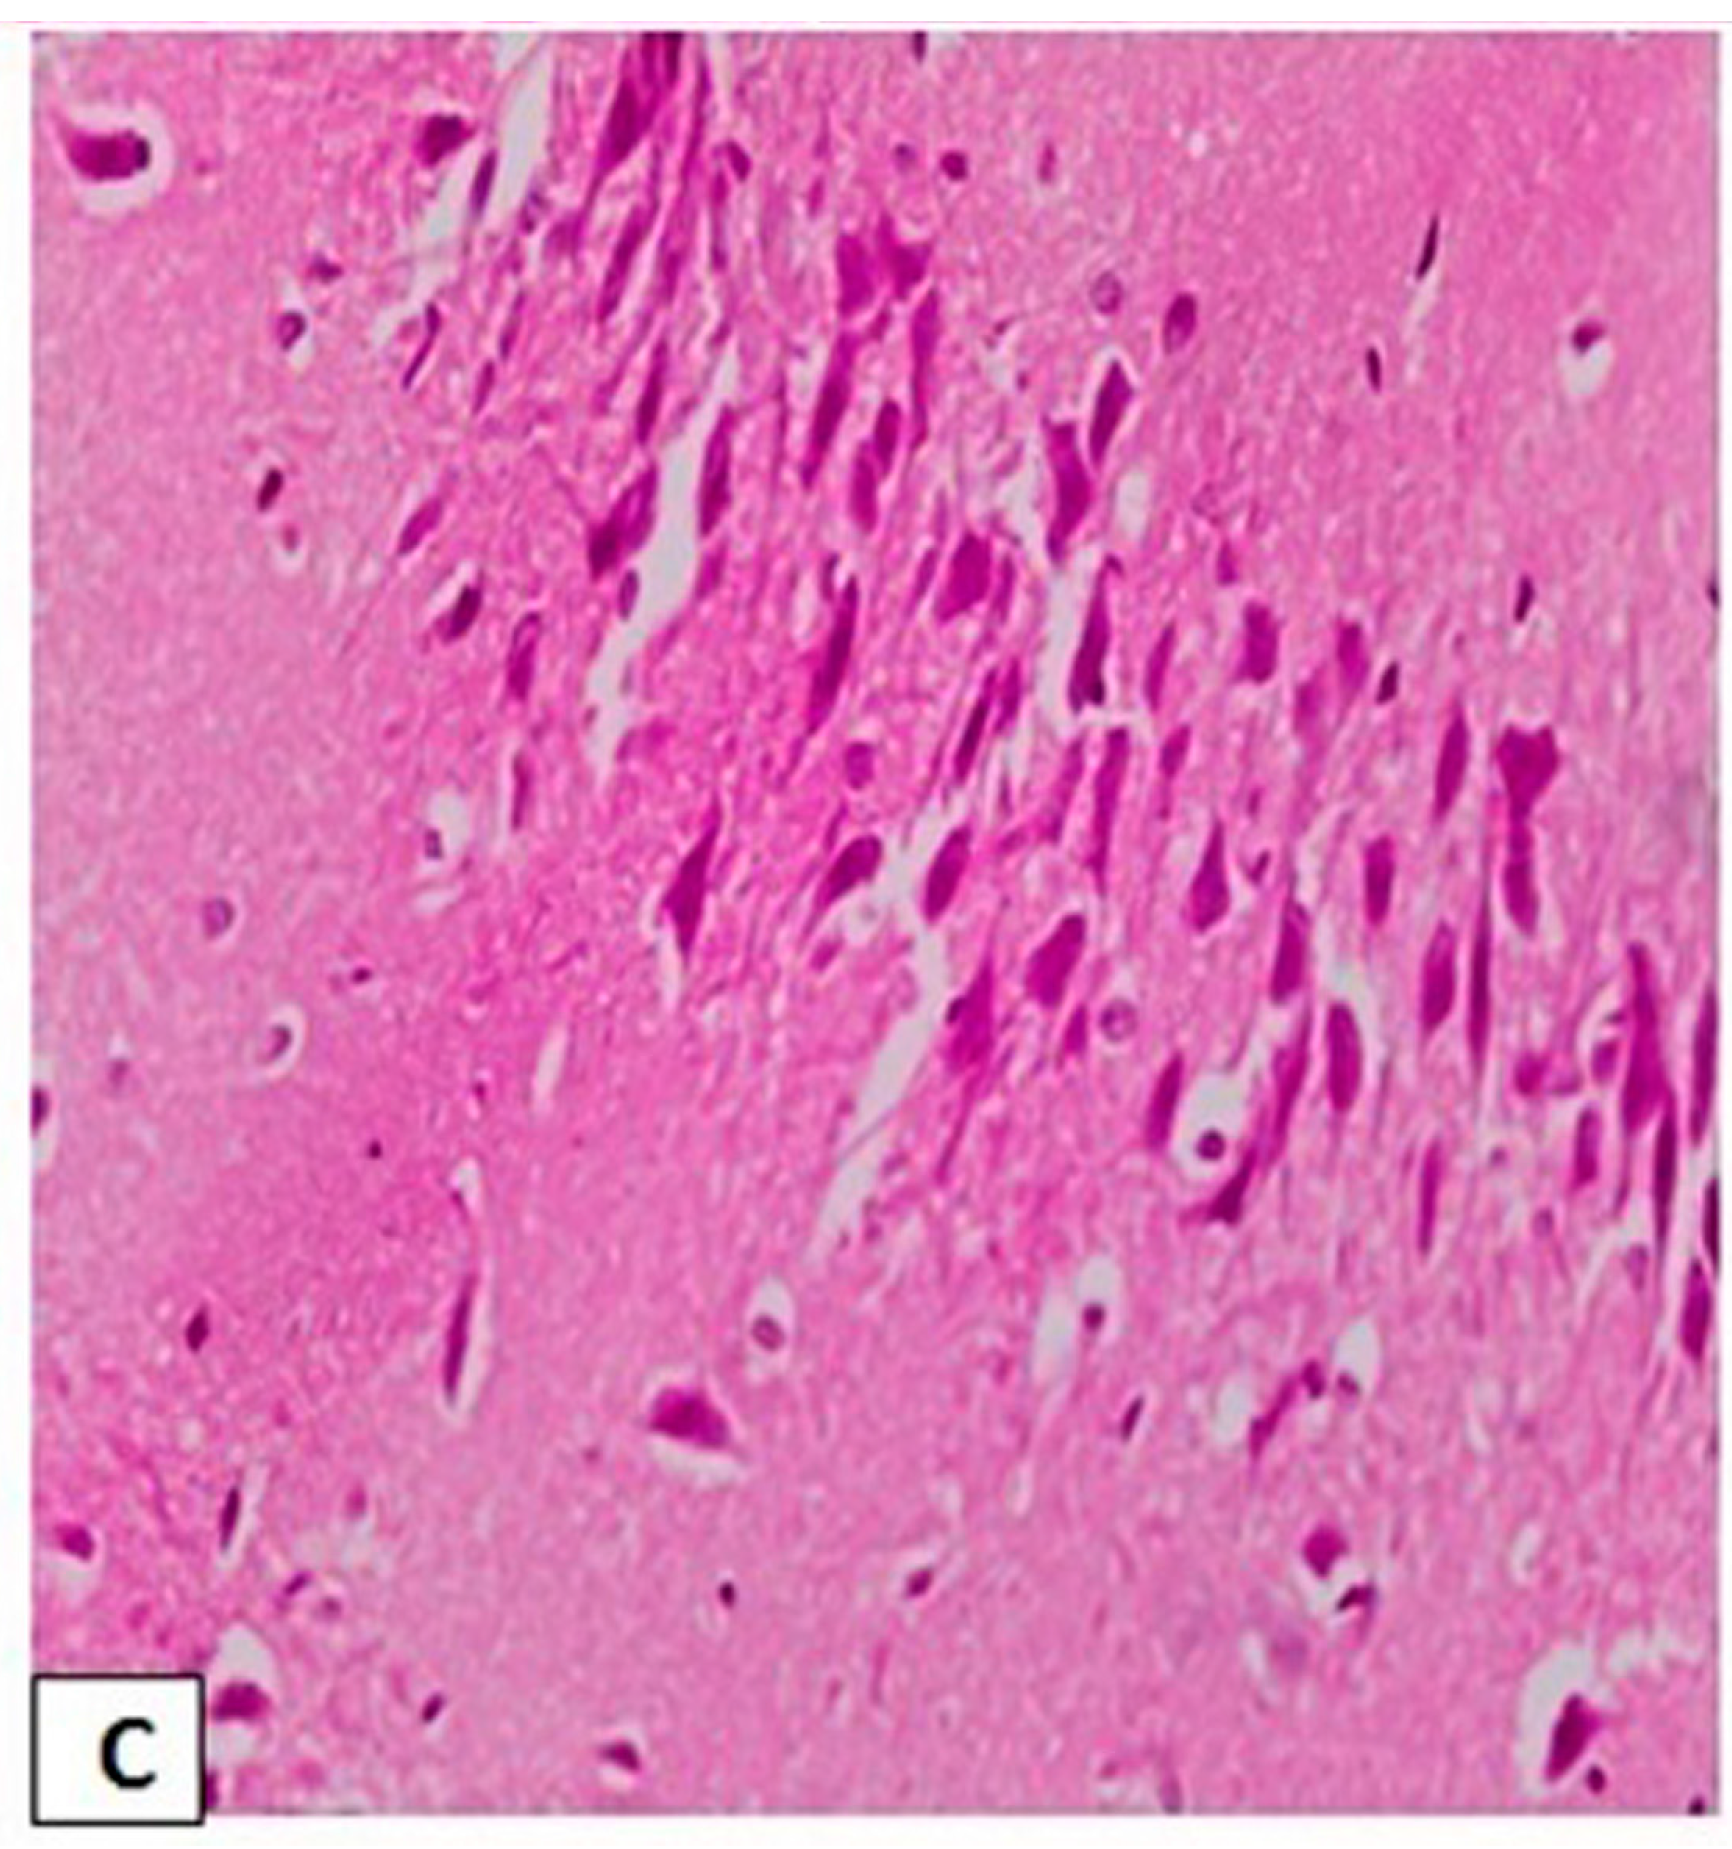

3.3. Effects of l-Car on the Morphology of Neurons in the CA3 Region of Hippocampus

3.4. Effects of l-Car on Hsp70 and LC3 Expression in the CA3 Region of Hippocampus